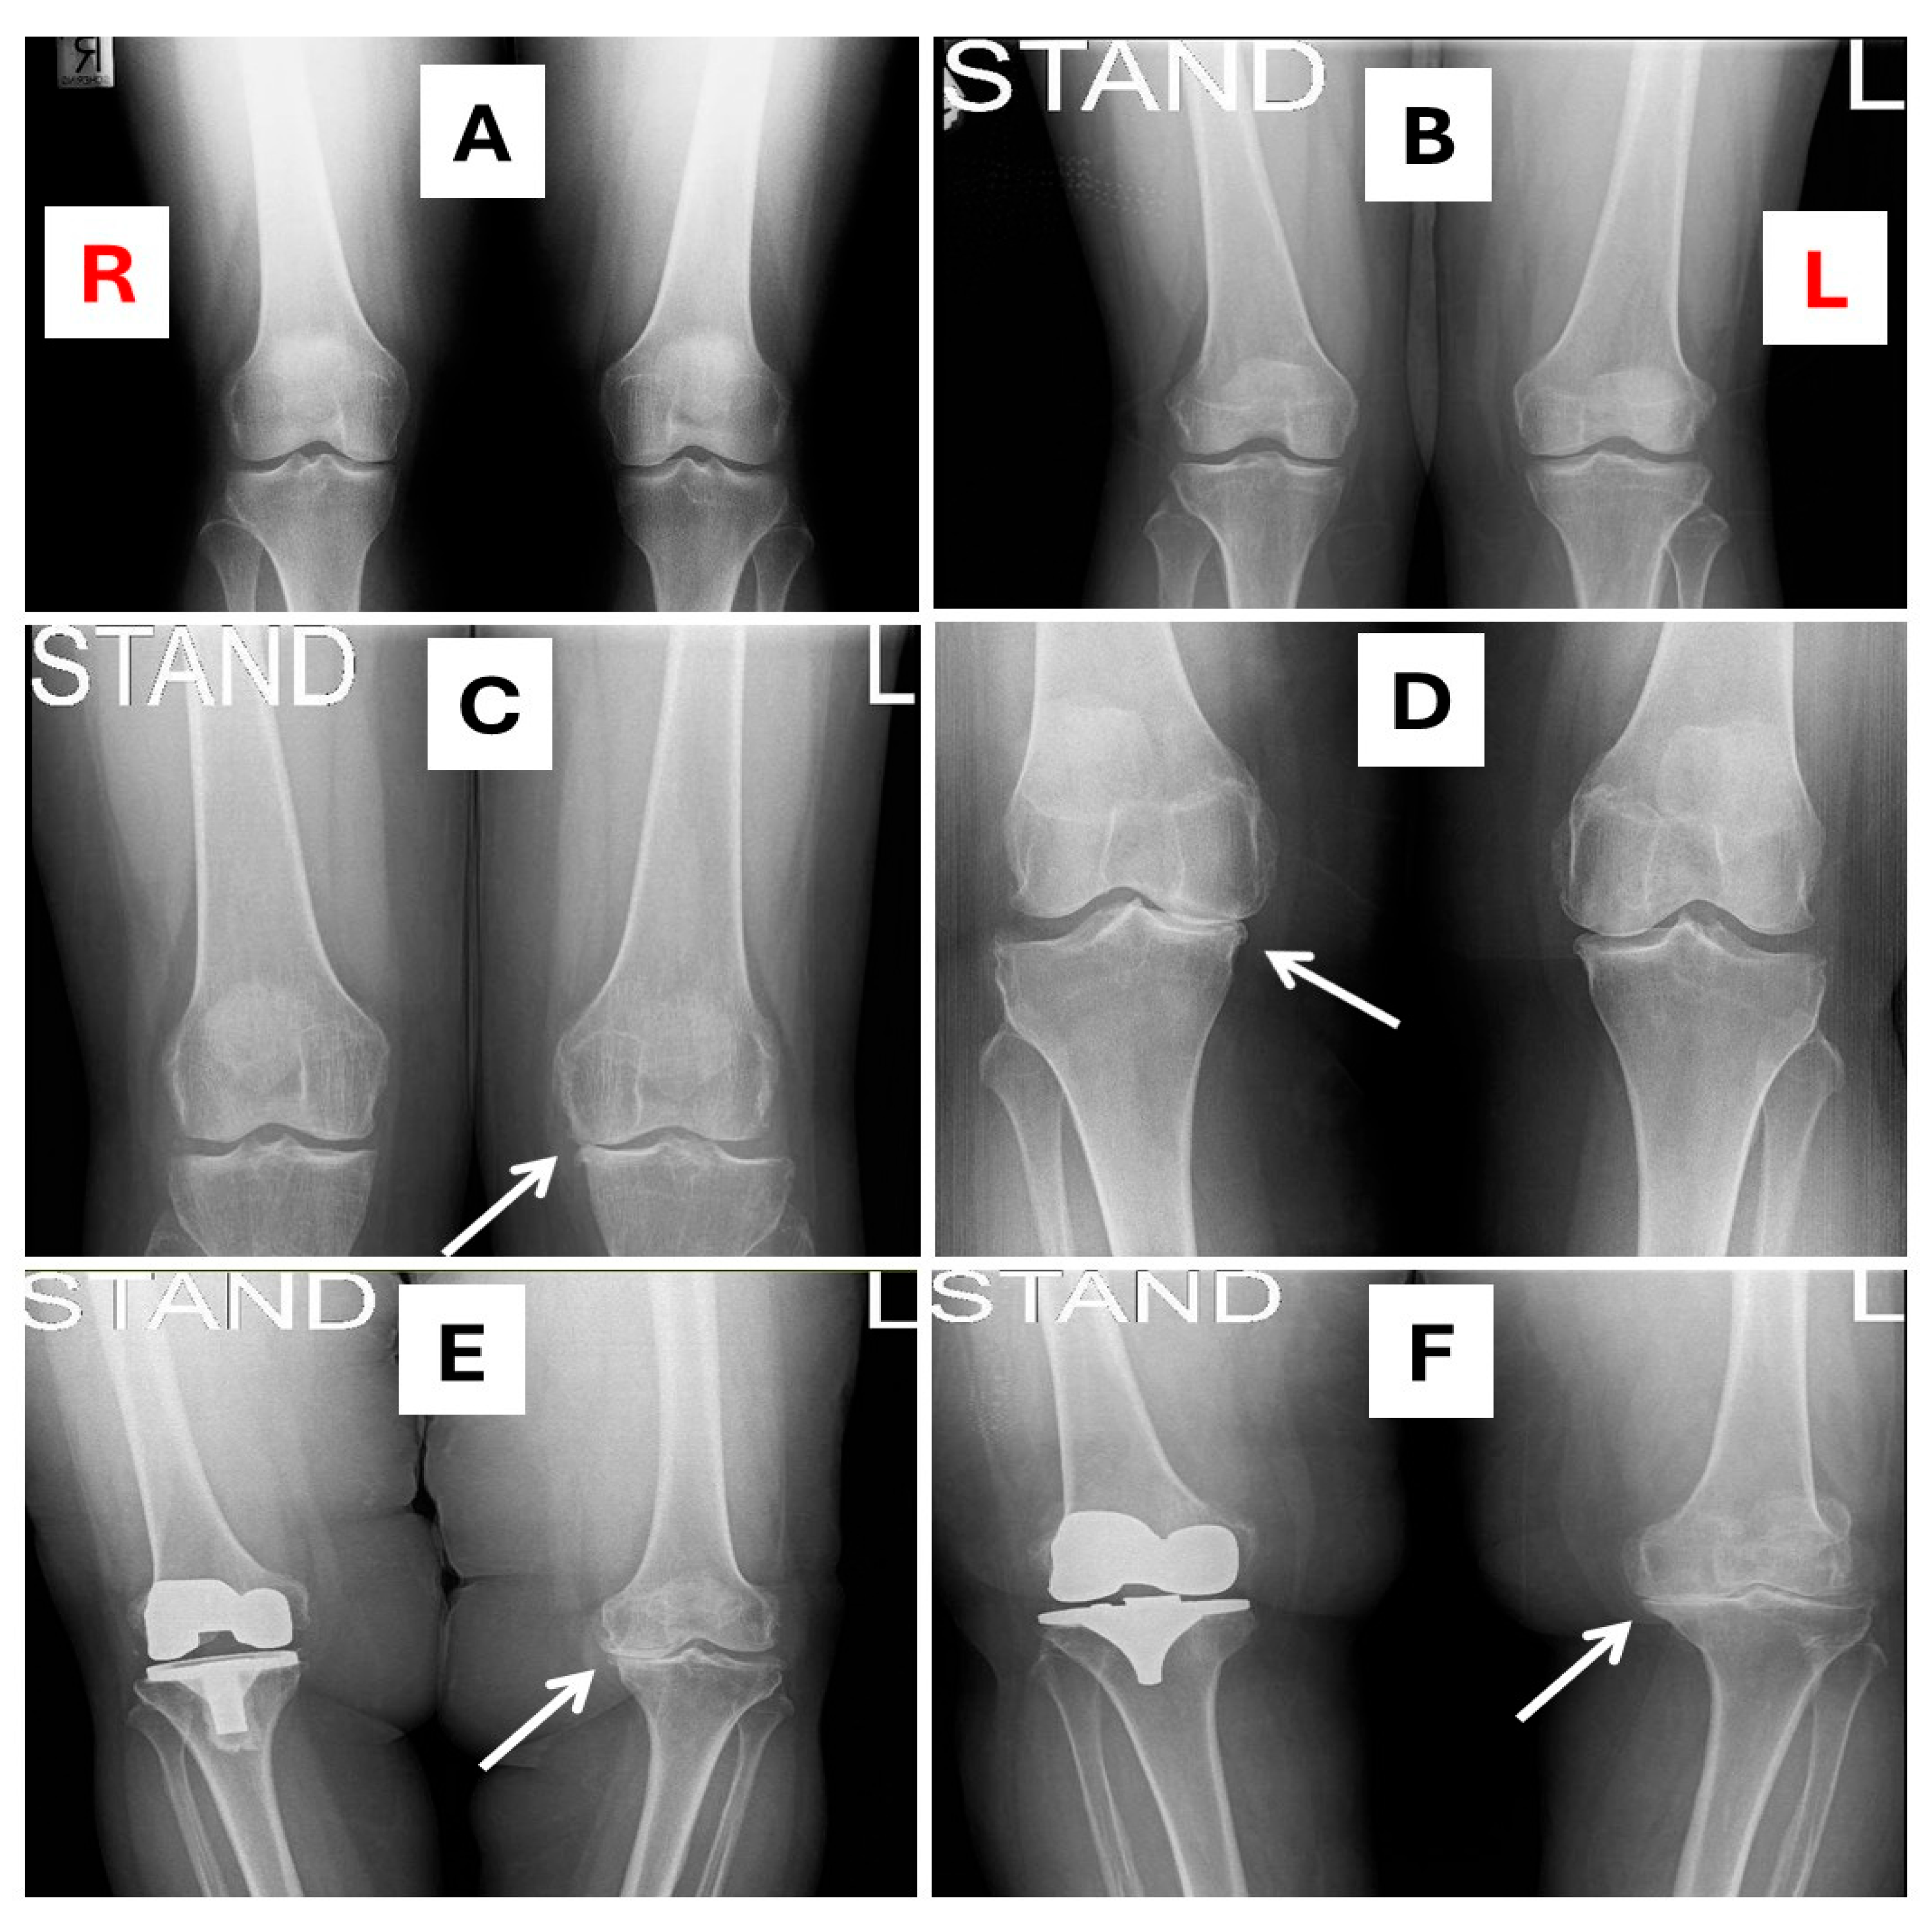

2.6. X-Ray Images of KOA